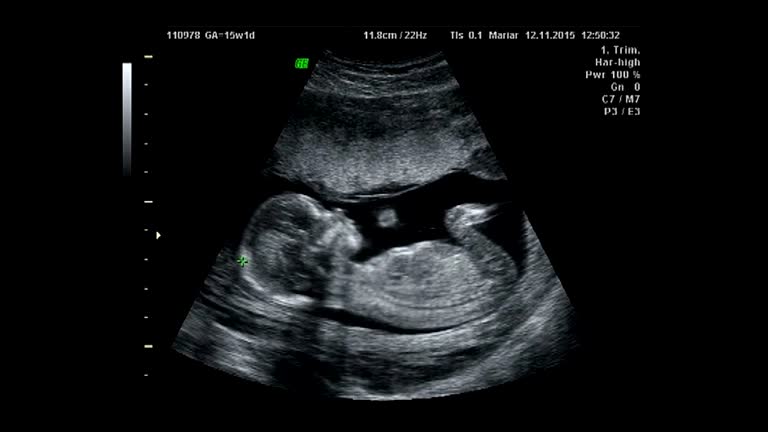

رشد جنین در ماه ششم بارداری

از ابتدای بارداری تا پایان ماه پنجم، جنین مسیر رشد شگفتانگیزی را پشت سر گذاشته است؛ او از یک سلول کوچک به موجودی با اندامهای شکلگرفته تبدیل میشود که میتواند حرکت کند، به صدا واکنش نشان دهد و حتی الگوی منظم خواب و بیداری داشته باشد. حالا در شش ماهگی بارداری، رشد و تکامل او وارد مرحلهای مهمتر میشود.

در این ماه، وزن جنین حدود 680 گرم است و قد او به حدود 30 سانتیمتر میرسد. اندامهای داخلی بهسرعت در حال تکامل هستند؛ بهویژه، ریهها شروع به تولید مادهای به نام سورفکتانت میکنند که برای تنفس پس از تولد ضروری است. در ادامه جزئیات بیشتری از هفتههای 21 تا 24 بارداری، یعنی ماه ششم در اختیارتان میگذاریم.